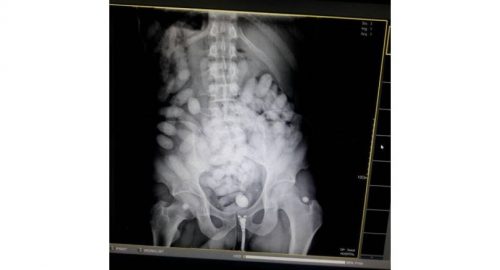

A Brazilian has been arrested after he allegedly smuggled cocaine into the country. An x-ray found that he had swallowed 100 packs of cocaine, totaling about 1.3 kilograms in an attempt to bring them into the country.

An X-ray found 100 oval-shaped objects inside his body. Police said he confessed to swallowing the packed cocaine while in Ethiopia and was supposed to meet a man who would pick up the drug in Bangkok.